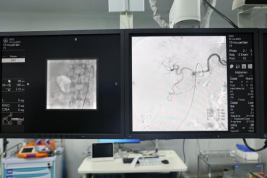

肝动脉造影显示肿瘤供血动脉 栓塞后血供消失